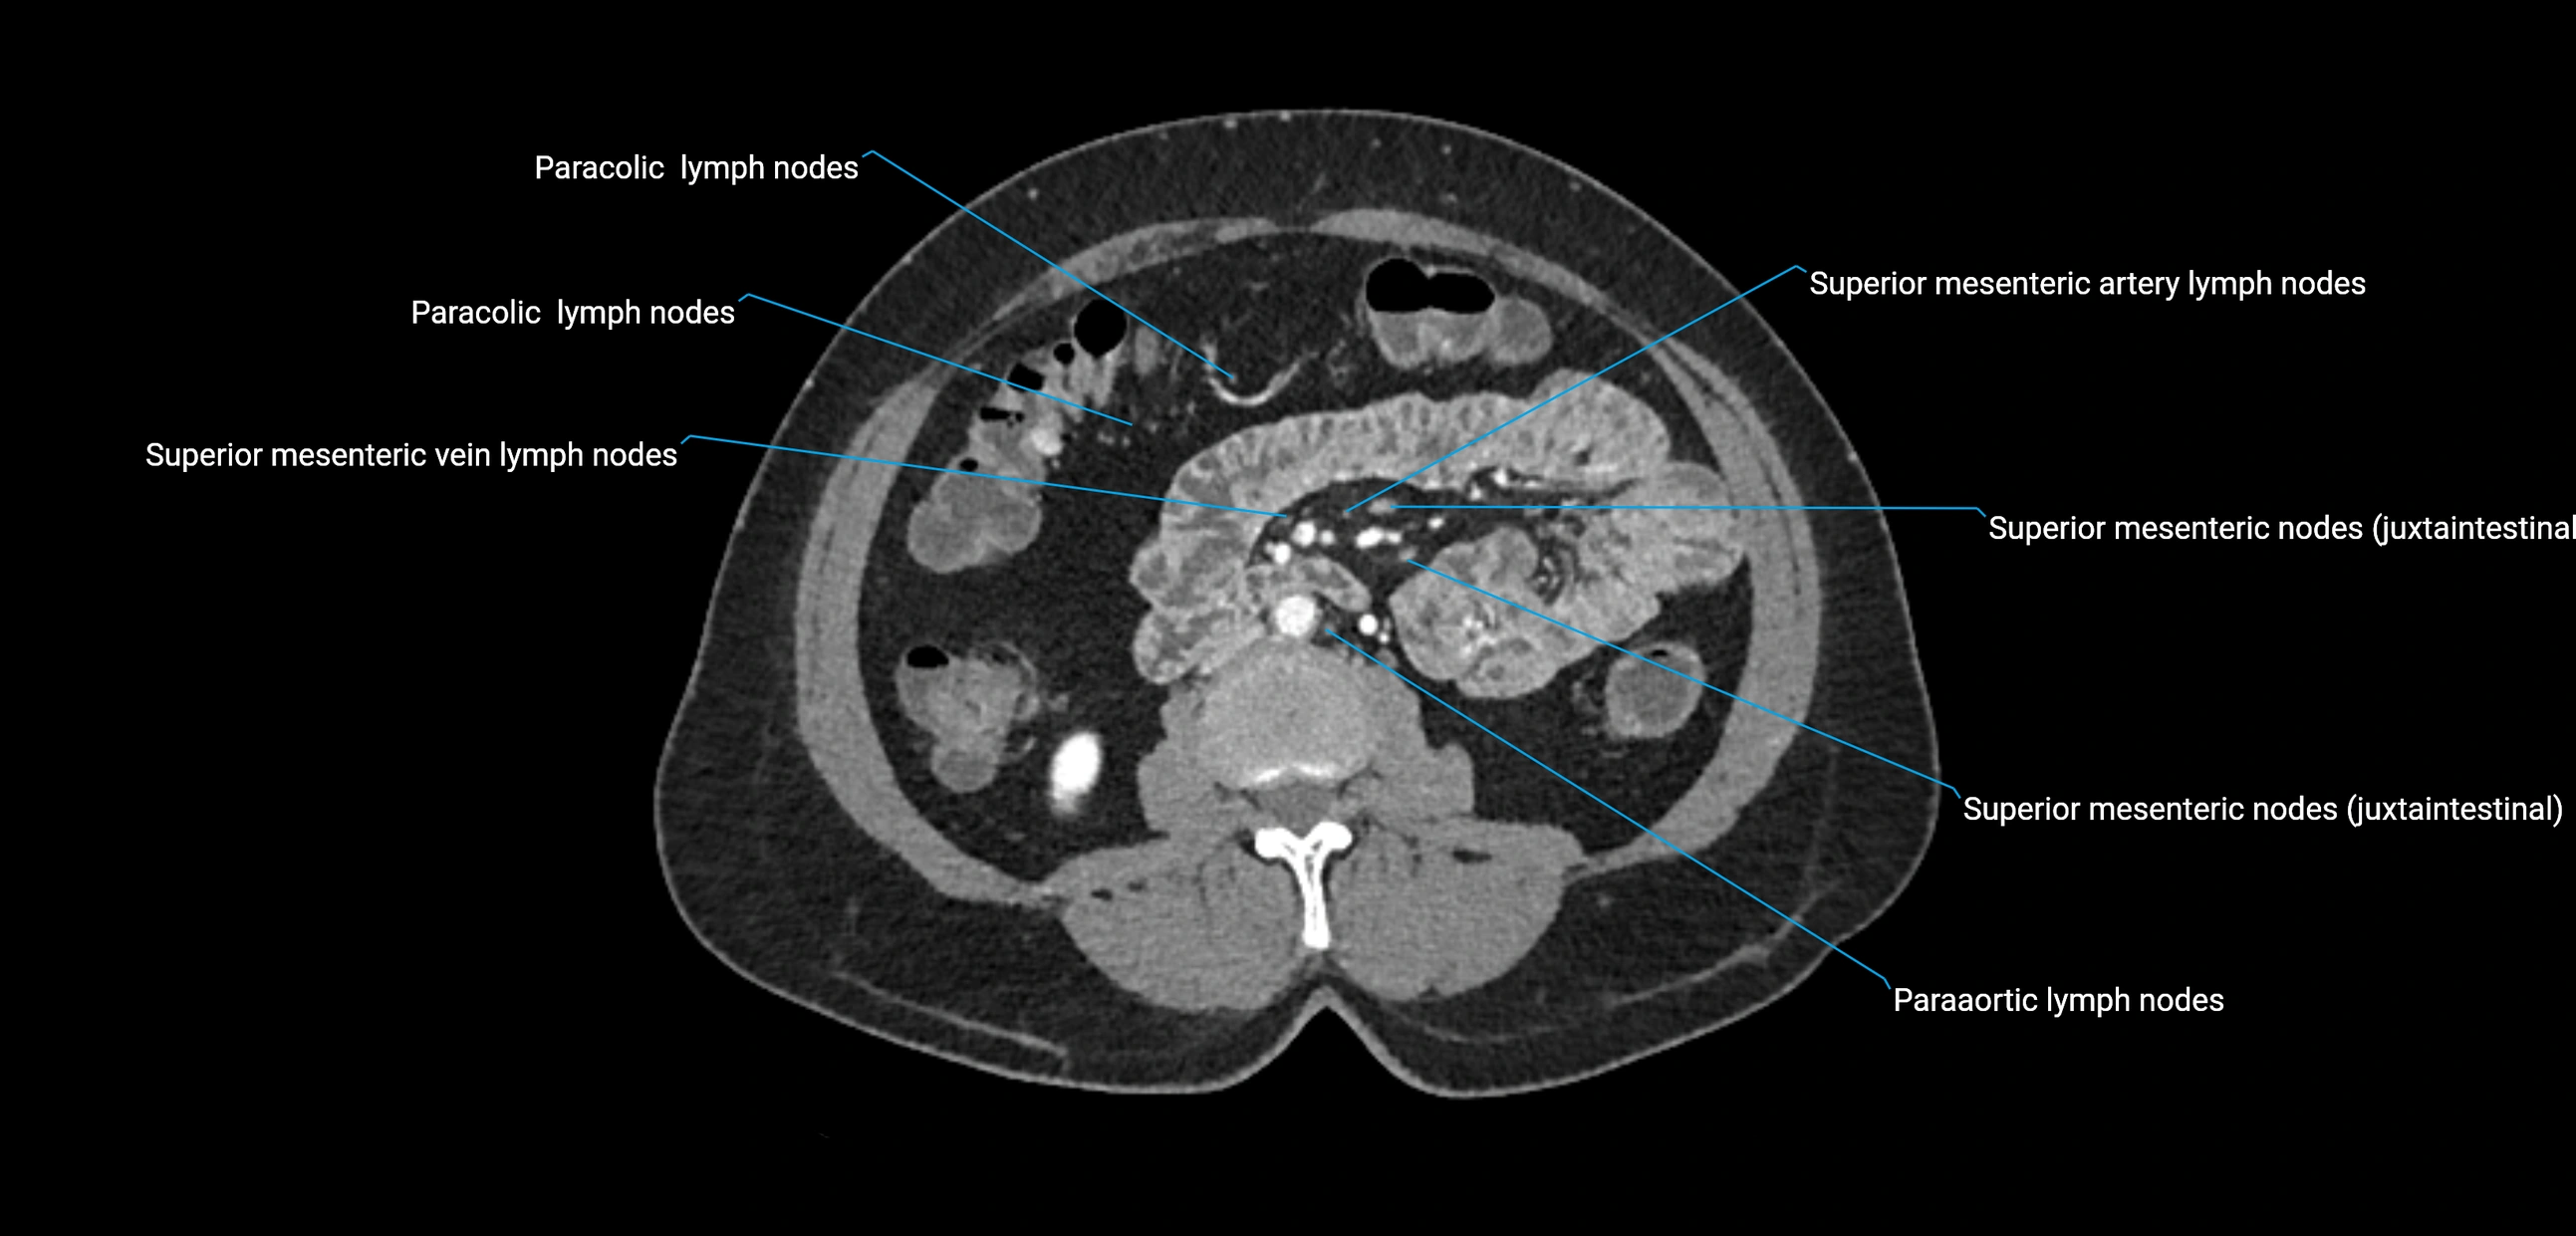

CT Appearance

CT Pre-Contrast:

• Nodes appear as soft-tissue density nodules adjacent to the aorta and IVC

• Calcification may be seen in chronic infections (e.g., tuberculosis)

CT Post-Contrast:

• Normal nodes enhance homogeneously

• Malignant nodes may show heterogeneous enhancement, central necrosis, or conglomerate formation

• Size >1 cm short axis is suspicious, though morphology and distribution are equally important